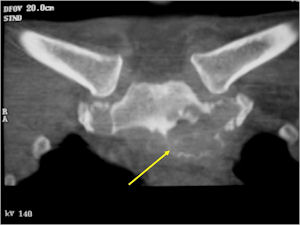

Sites:

- Spine (40% of cases; usually posterior elements)

- Long Bones (30%; Most arise from diaphysis or metaphysis; Epiphyseal lesions are rare but may occur more often in the tubular bones of the hands or feet)

CT Scan:

- More useful for detecting mineralization and evaluating extent of bone destruction than plain X-ray